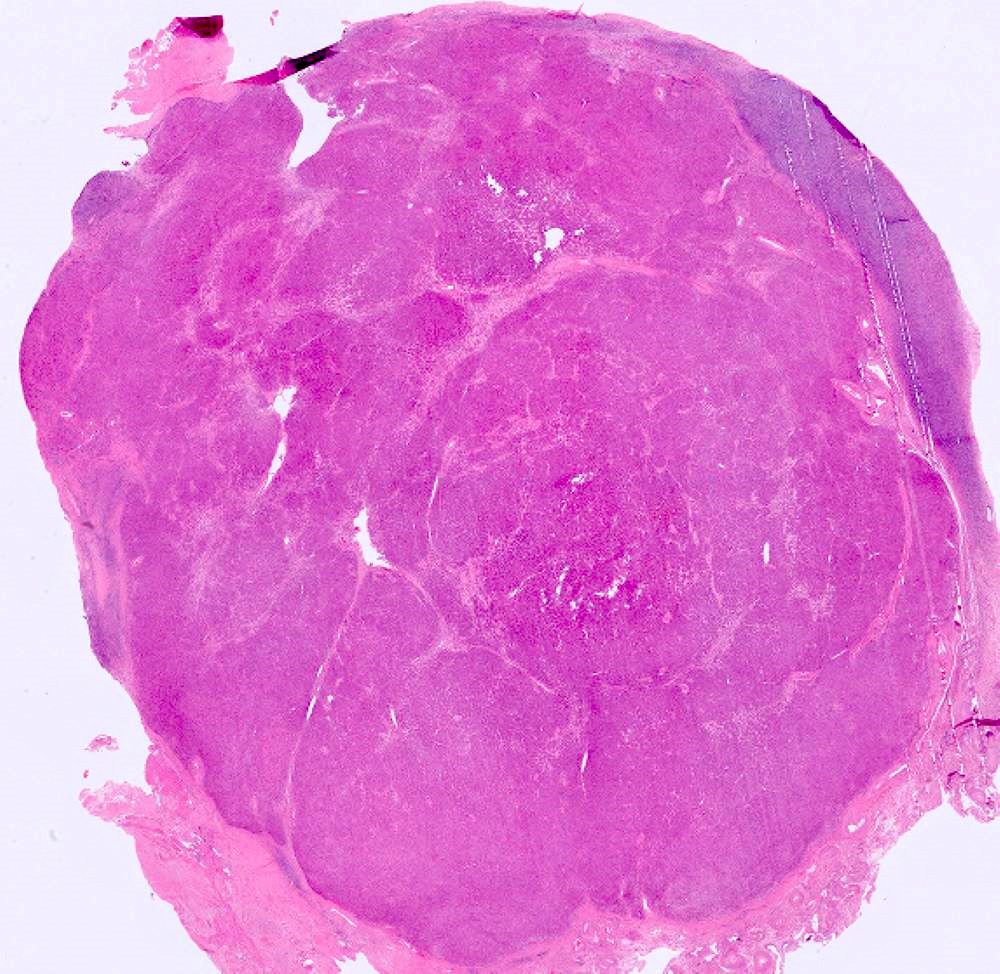

Lipoblastoma •Benign neoplasm of embryonal white fat •May be local or diffuse (lipoblastomatosis) •75-90% occur<3y/o •Trunk+extremities are most common sites •Size usually 2-5 cm •🔬lobulated; adipocytes w/ variable maturation; separated by fibrovascular septae •🧬PLAG1

Lipoblastoma

•Benign neoplasm of embryonal white fat

•May be local or diffuse (lipoblastomatosis)

•75-90% occur&lt;3y/o

•Trunk+extremities are most common sites

•Size usually 2-5 cm

•🔬lobulated; adipocytes w/ variable maturation; separated by fibrovascular septae

•🧬PLAG1